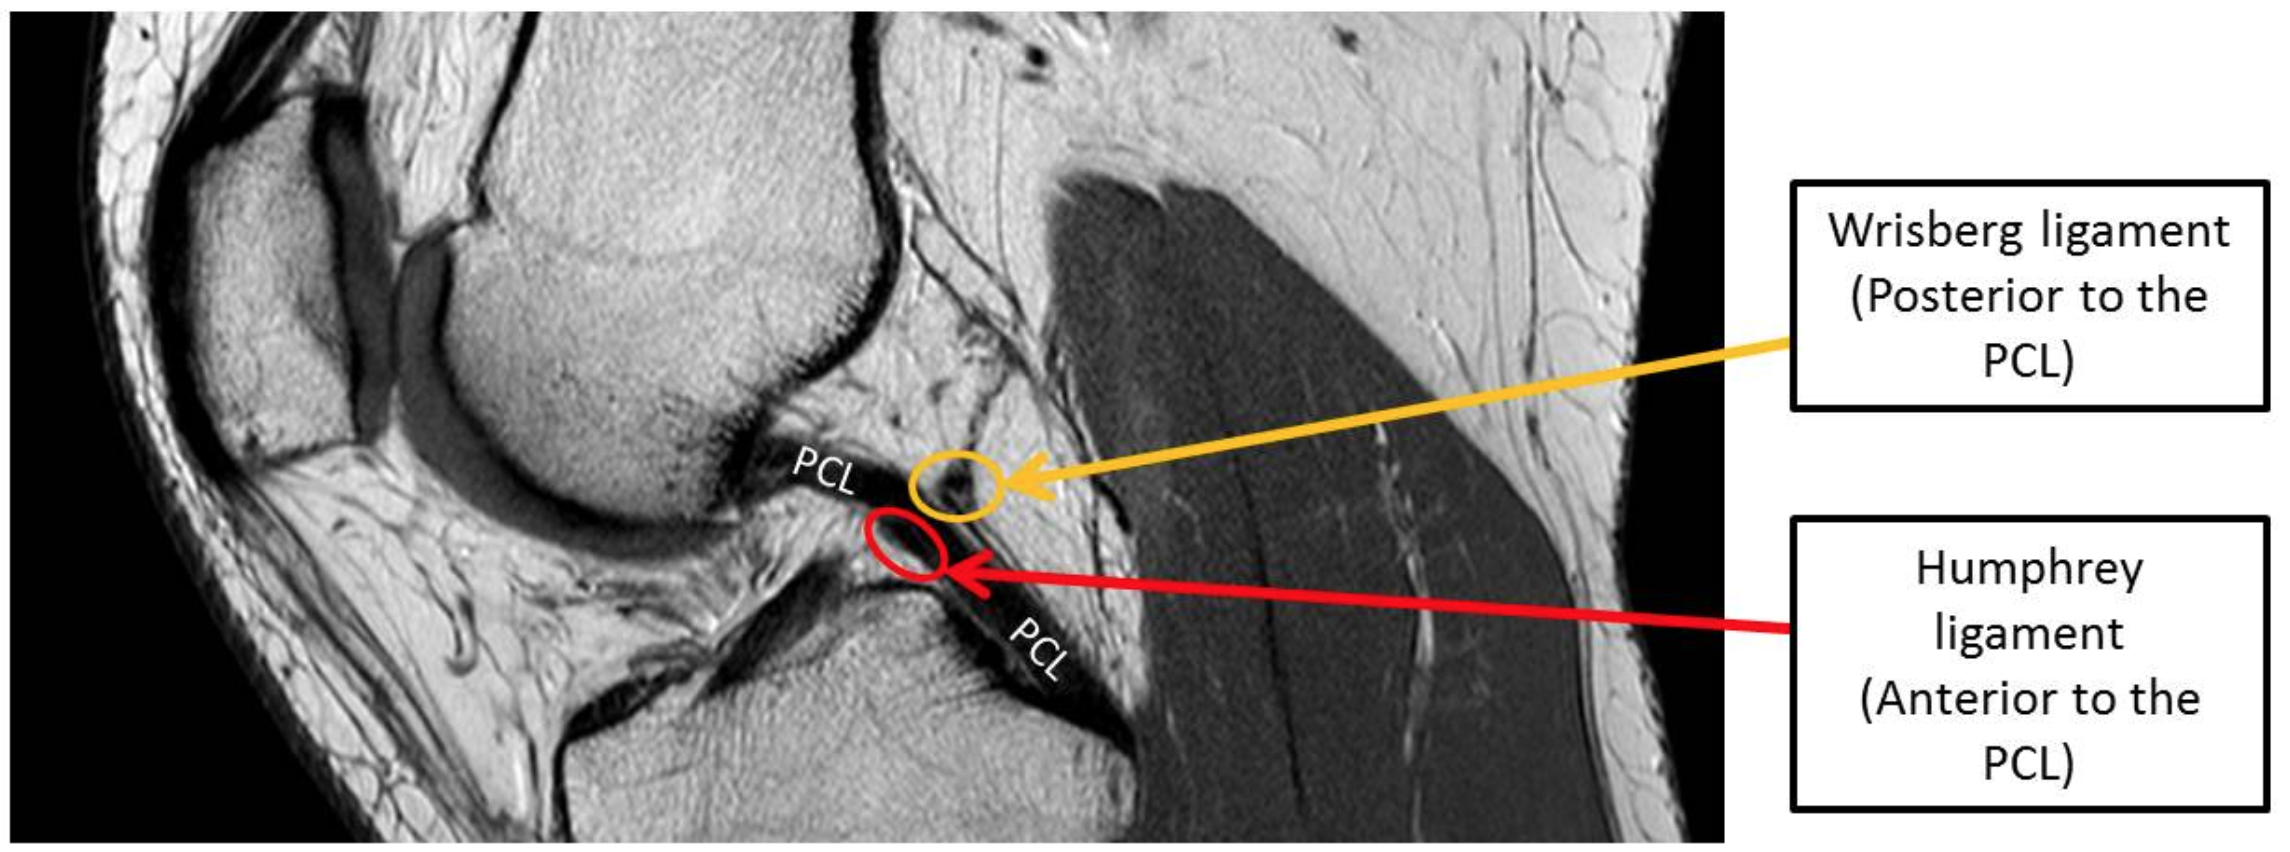

Posterior meniscofemoral ligament = Wrisburg = posterior to PCL

• Can have bifurcation that looks like a tear but is not

• Can have it terminate at mid portion of PCL and makes PCL look like it has a hump

Anterior meniscofemoral ligament = Humphrey = anterior to PCL